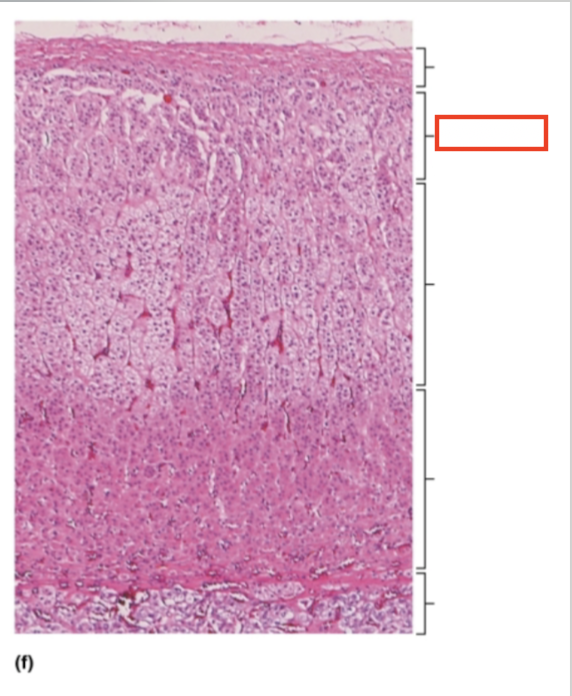

What structure is highlighted?

capsule

What structure is highlighted?

zona glomerulosa

What structure is highlighted?

zona fasciculata

What structure is highlighted?

zona reticularis

What structure is highlighted?

adrenal medulla

What tissue is shown?

adrenal gland